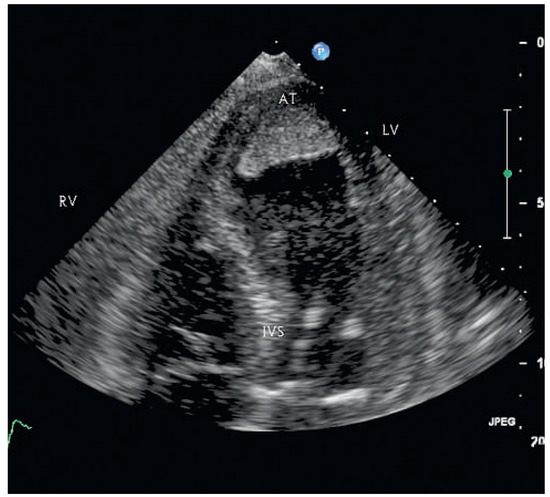

Since the first description of the athlete’s heart in 1899 by Henschen and Darling, the knowledge on cardiovascular adaptations to exercise conditioning h as expanded considerably. There is an ongoing debate about the true nature of the athlete’s hea...